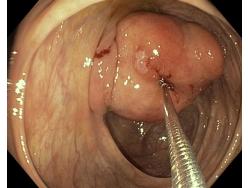

Nowotwory przewodu pokarmowego

Zabiegi endoskopowe